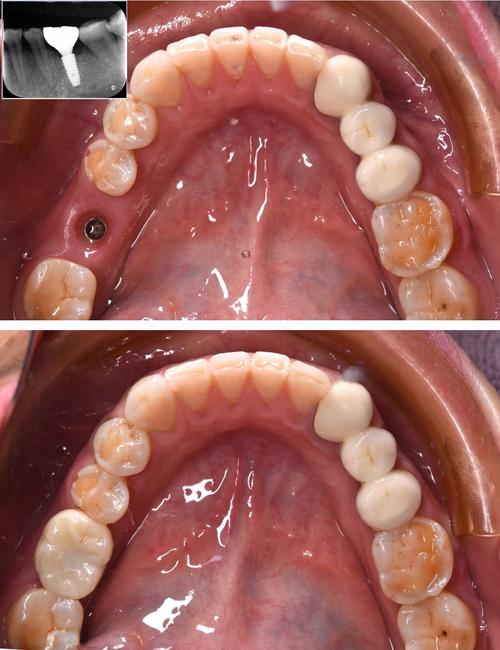

为规避风险,患者需从多维度筛选机构,首先核查资质,确保机构具备口腔种植专科资质,医生持有《医师资格证书》和《医师执业证书》,且种植牙案例不少于500例,其次考察医生背景,优先选择有公立医院工作经历、擅长复杂病例(如骨量不足、全口种植)的医生,可通过面诊时询问其具体案例和手术方案细节判断专业性,设备方面,确认机构是否配备CBCT、种植机、无菌手术室等必备设备,数字化设备(如动态导航系统)是加分项,口碑评价可通过第三方平台(如卫健委官网、大众点评)查看患者真实反馈,重点关注是否有投诉记录及术后效果展示,要求机构提供书面报价单,明确种植体品牌、基台类型、牙冠材质及是否包含术后复查费用,避免隐形消费。